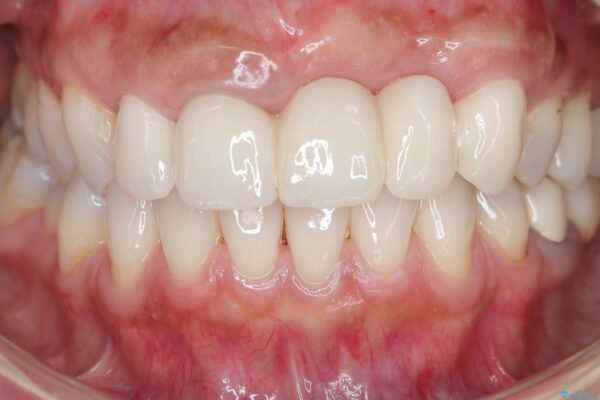

治療後

歯槽堤保存術を併用したブリッジ治療 治療後画像 歯槽堤保存術を併用したブリッジ治療 治療後画像 歯槽堤保存術を併用したブリッジ治療 治療後画像 歯槽堤保存術を併用したブリッジ治療 治療後画像 歯槽堤保存術を併用したブリッジ治療 治療後画像 歯槽堤保存術を併用したブリッジ治療 治療後画像 歯槽堤保存術を併用したブリッジ治療 治療後画像